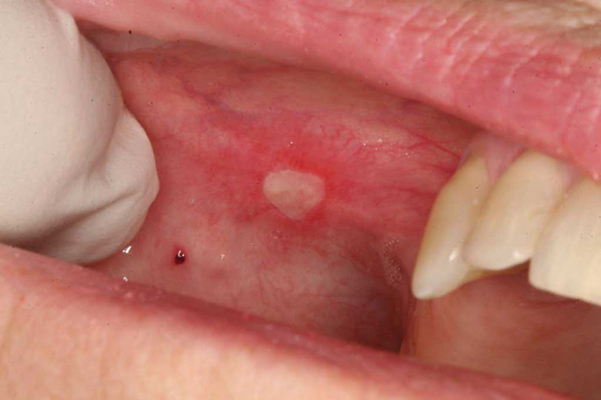

口腔癌圖片

口腔癌的前兆 (37)

口腔癌的前兆 (38)

口腔癌的前兆 (39)

口腔癌的前兆 (4)

口腔癌的前兆 (40)